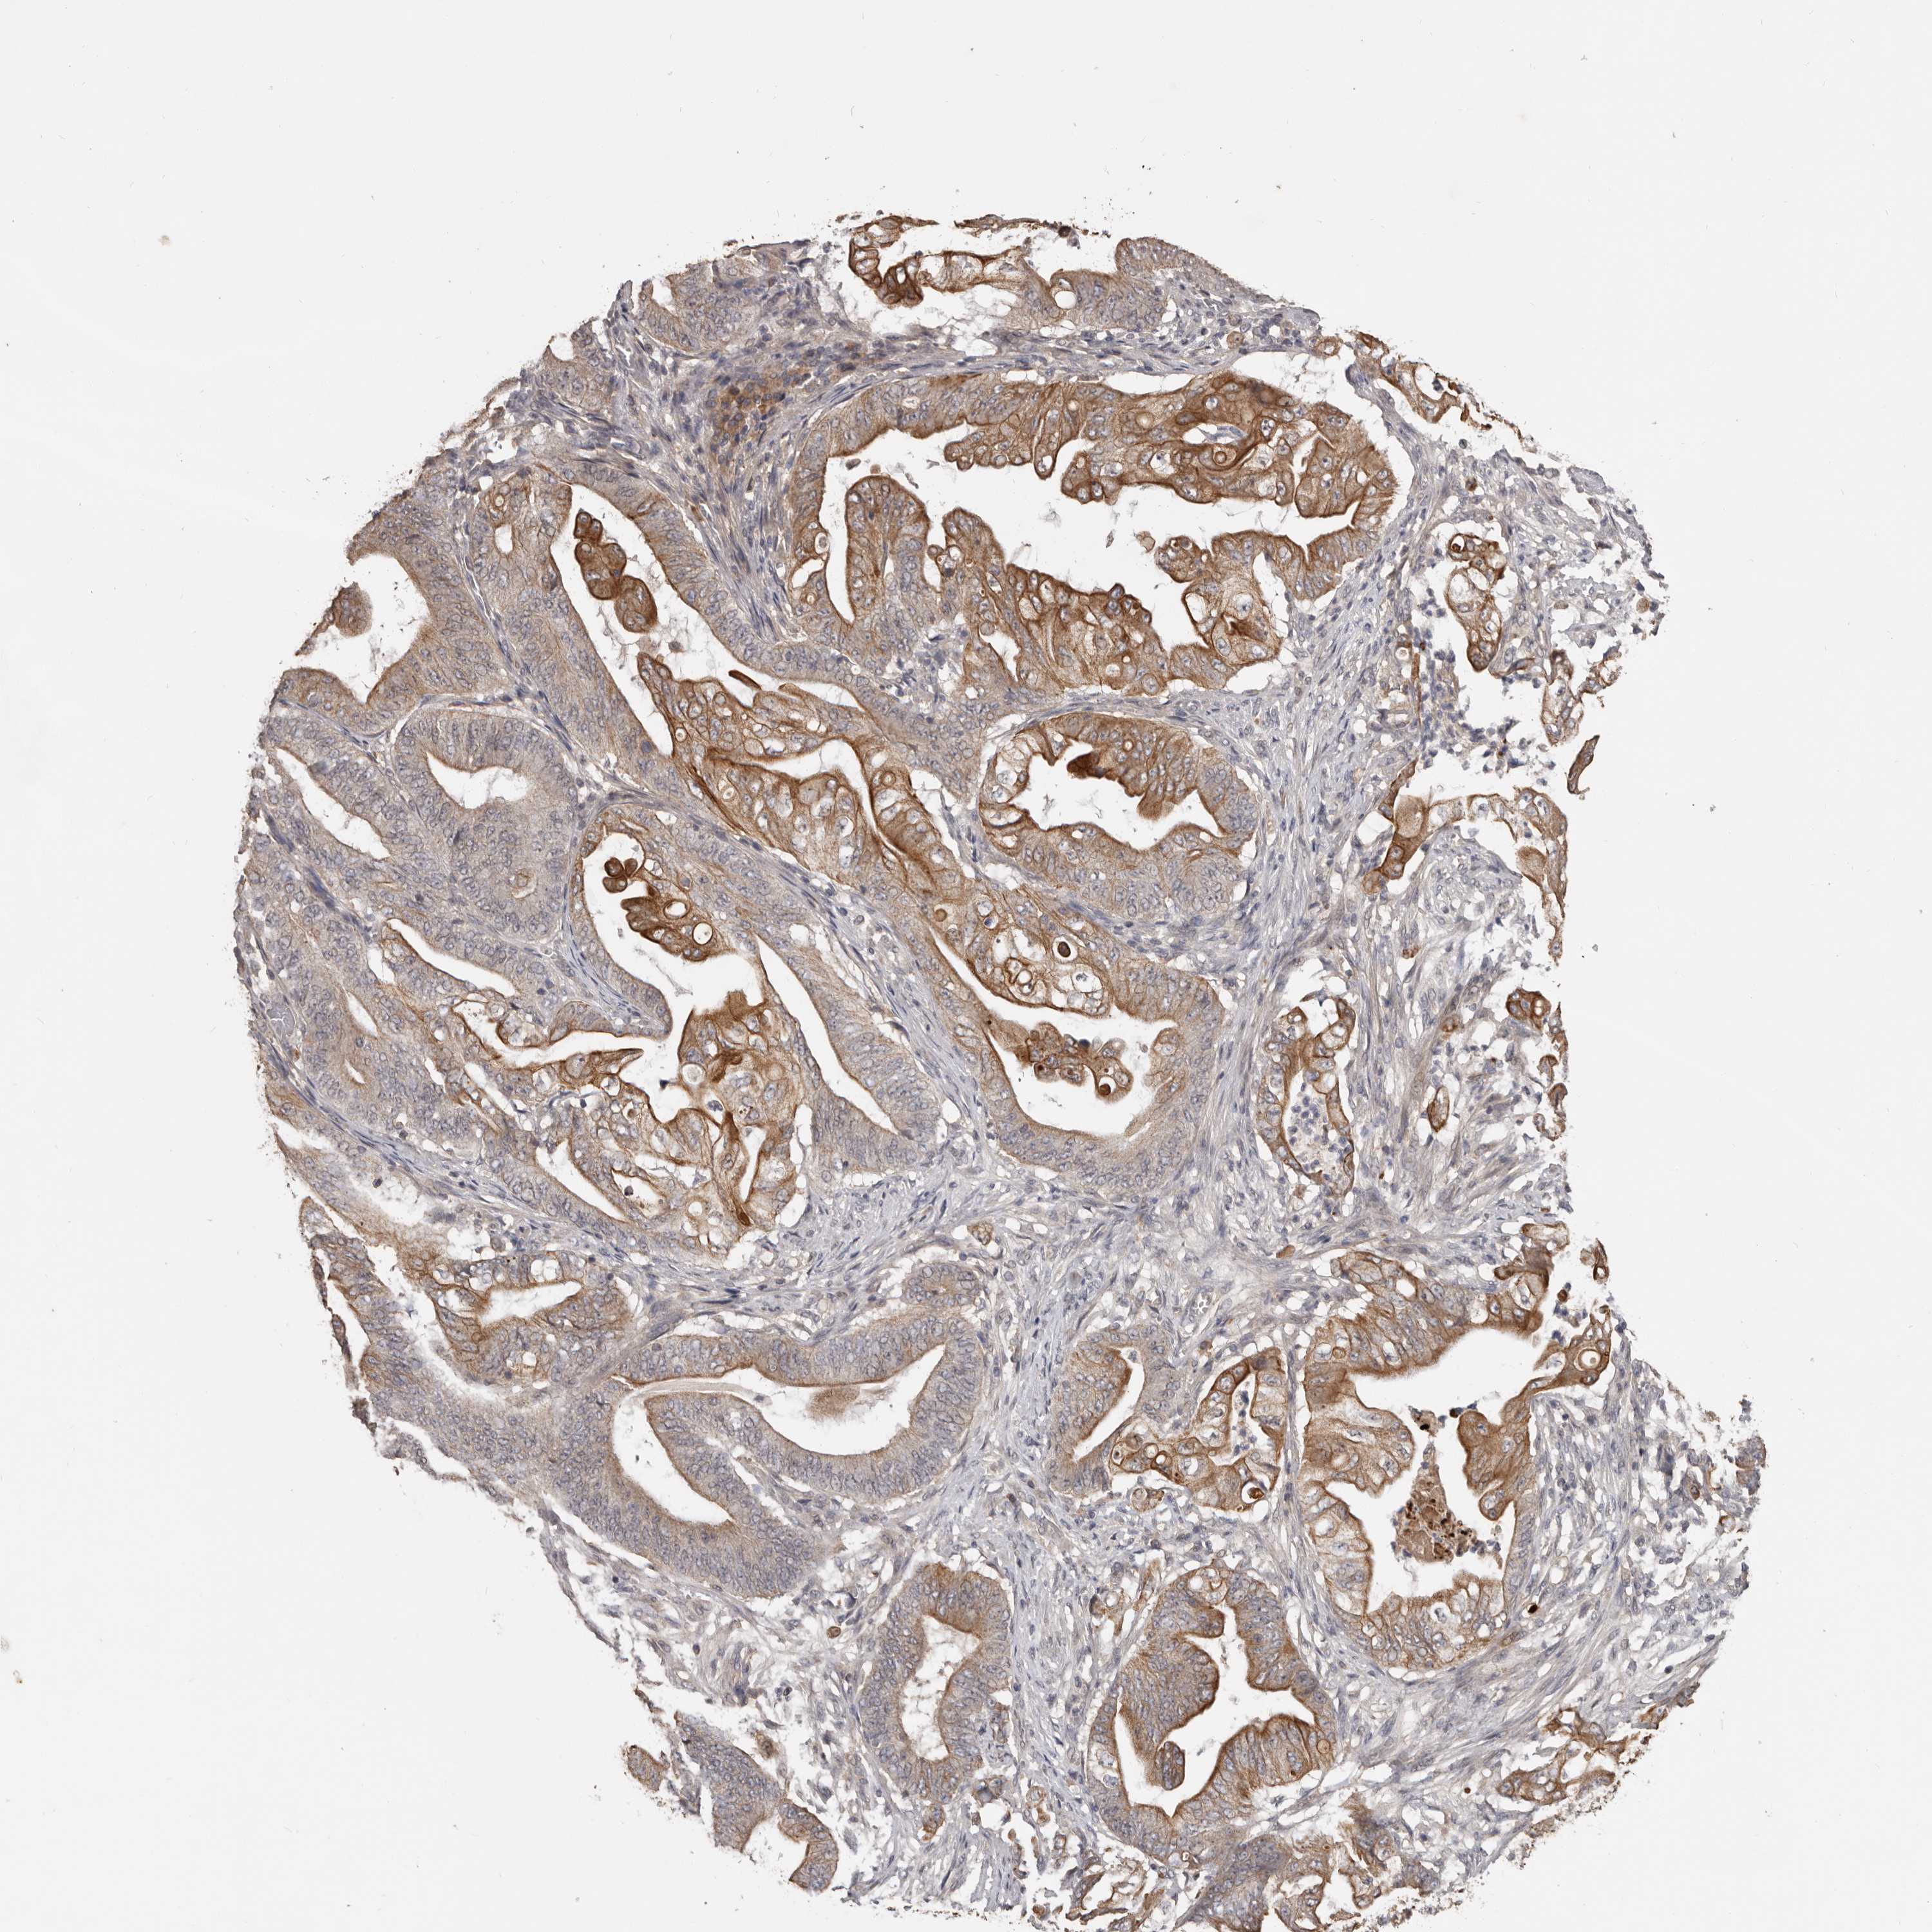

STOMACH CANCER - Protein expressioni

A mouse-over function shows sample information and annotation data. Click on an image to view it in a full screen mode. Samples can be filtered based on level of antibody staining by selecting one or several of the following categories: high, medium, low and not detected. The assay and annotation is described here.

Note that samples used for immunohistochemistry by the Human Protein Atlas do not correspond to samples in the TCGA dataset.

Antibody stainingi

Antibody staining in the annotated cell types in the current human tissue is reported as not detected, low, medium, or high, based on conventional immunohistochemistry profiling in selected tissues. This score is based on the combination of the staining intensity and fraction of stained cells.

Each image is clickable and will lead to virtual microscopy that enables deeper exploration of all samples and also displays staining intensity scores, fraction scores and subcellular localization as well as patient and tissue information for each sample.

Antibody HPA027895

Staining

High

Medium

Low

Not detected

Intensity

Strong

Moderate

Weak

Negative

Quantity

>75%

75%-25%

<25%

None

Location

Nuclear

Cytoplasmic/membranous

Cytoplasmic/membranous,nuclear

Adenocarcinoma, NOS